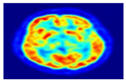

2.2.1. Positron Emission Tomography (PET)

2.2.2. Single Photon Emission Computed Tomography (SPECT)